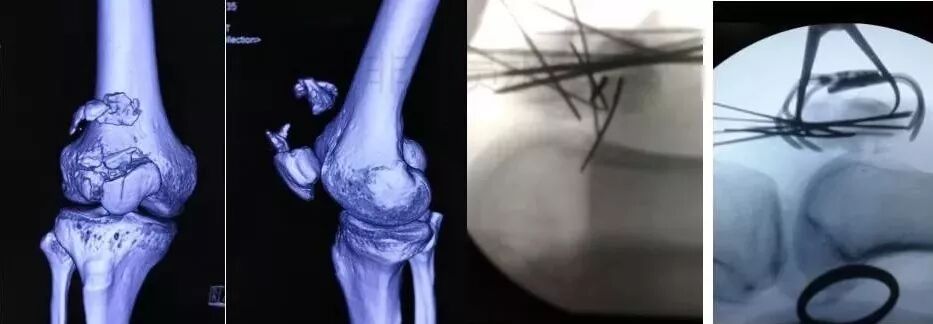

3)髋臼骨折(伤后5-7天)

图片

• 人体最大的负重关节,精确复位可达到关节的最佳匹配,确保正常力学性能;

• 影像学移位程度大,不匹配>2mm--手术;

• 髋关节脱位,髋臼后壁骨折并股骨头骨折,复位后关节仍然不稳,或关节腔有游离骨块--手术。

并发症:异位骨化18-90%;股骨头坏死3-9%